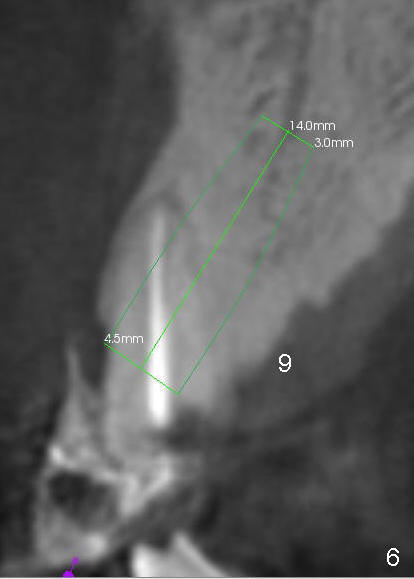

First molar occlusion is planned (1,2). The tooth #3 was extracted a year ago (Fig.1 (CT sagittal section). There is more bone loss distally so that bone graft (red circles) is required post implantation (5.3x14 mm). Buccolingual width is not severely compromised (Fig.2 (coronal section), 3).